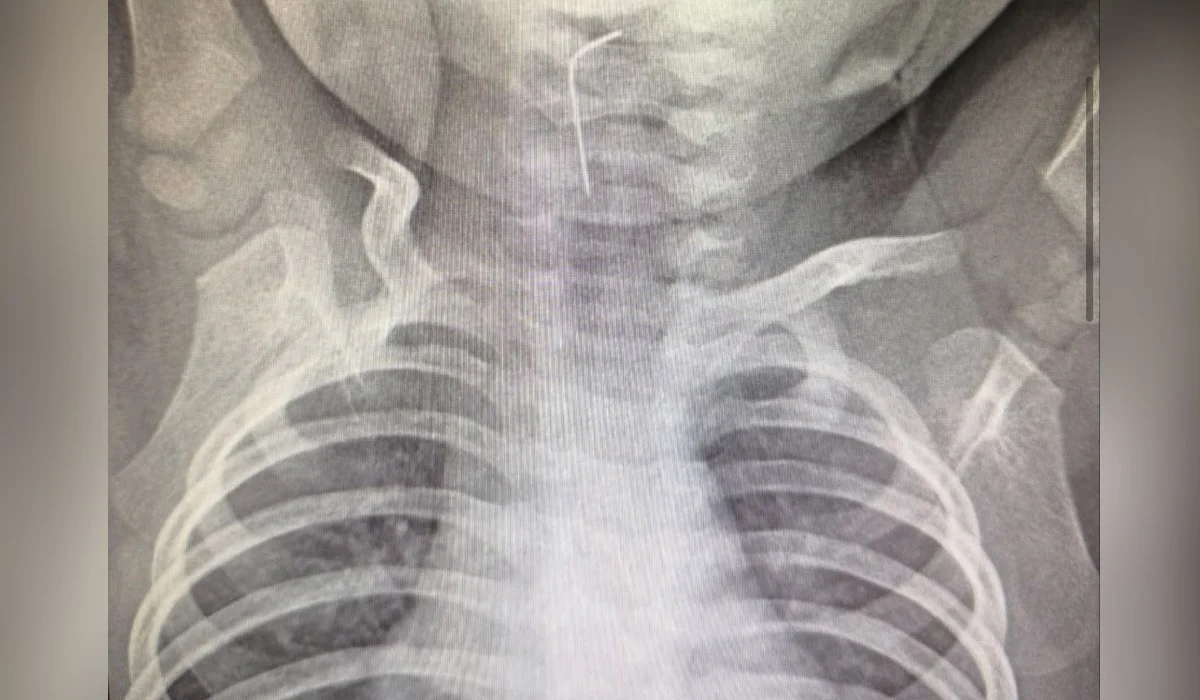

Девятимесячный малыш проглотил иглу в Туркестанской области

В Туркестанскую областную детскую больницу бригадой скорой помощи был экстренно доставлен девятимесячный ребенок, случайно проглотивший иглу, передает Azattyq Rýhy со ссылкой на пресс-службу акимата.

Врачи провели рентгенологическое обследование с применением эндоскопического метода. Специалистам удалось точно определить местонахождение инородного предмета и успешно извлечь иглу, застрявшую в пищеводе.